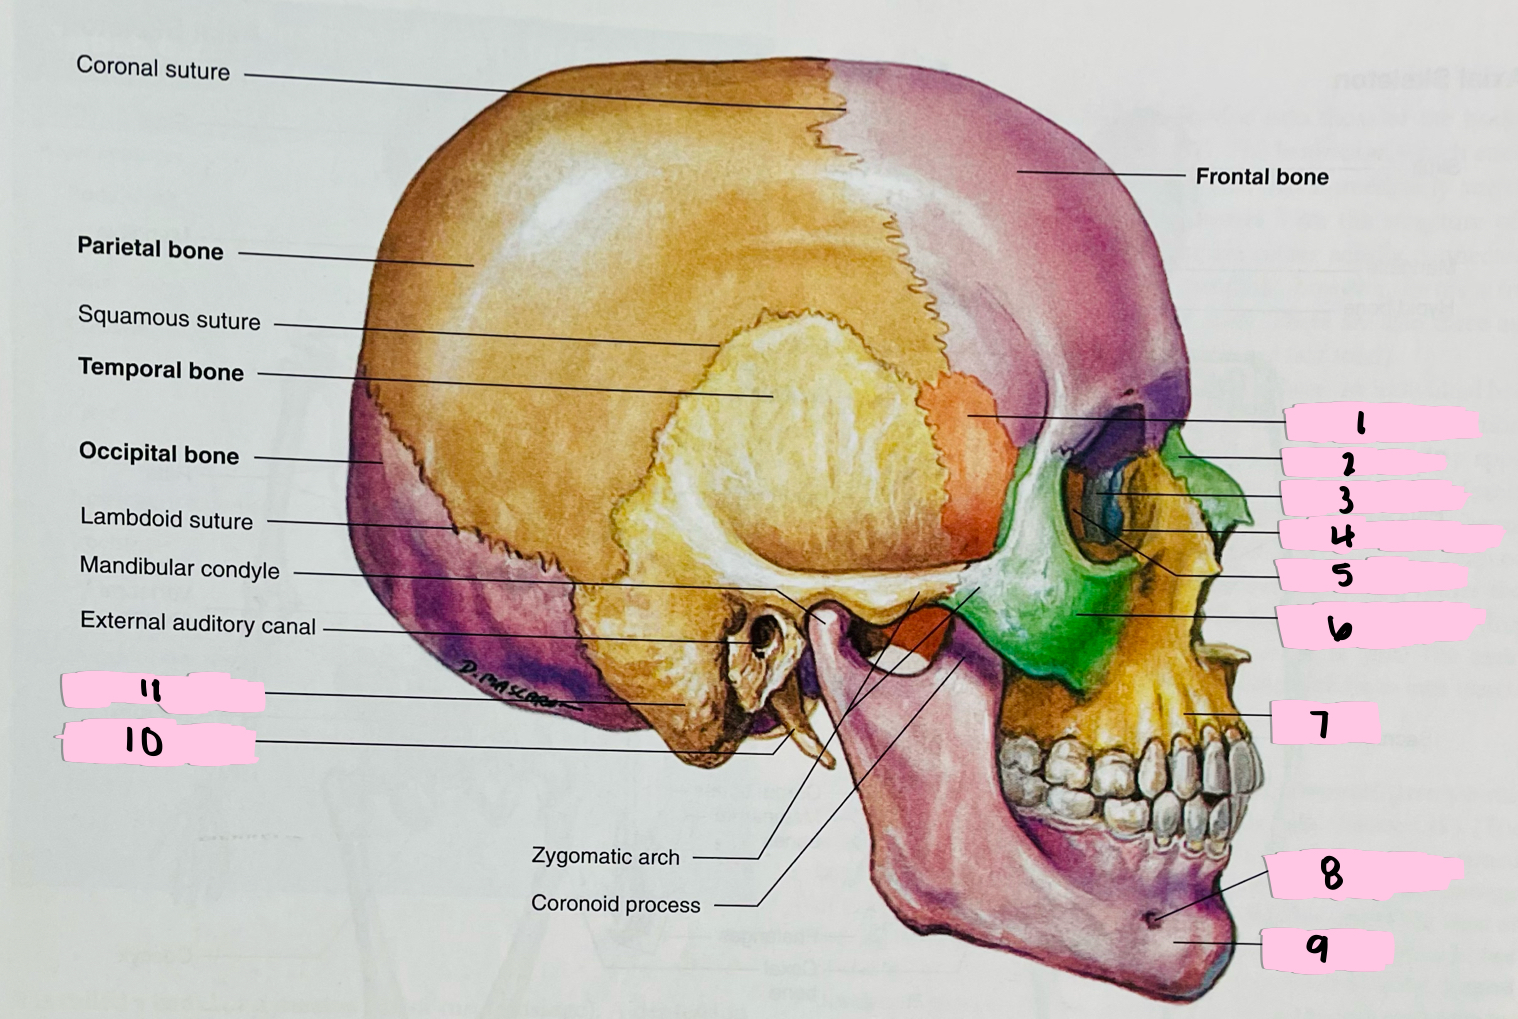

What is 1 pointing to?

Sphenoid bone

What is 2 pointing to?

Nasal bone

What is 3 pointing to?

Lacrimal bone

What is 4 pointing to?

Nasolacrimal canal

What is 5 pointing to?

Ethmoid bone

What is 6 pointing to?

Zygomatic bone

What is 7 pointing to?

Maxilla

What is 8 pointing to?

Mental foramen

What is 9 pointing to?

Mandible

What is 10 pointing to?

Styloid process

What is 11 pointing to?

Mastoid process